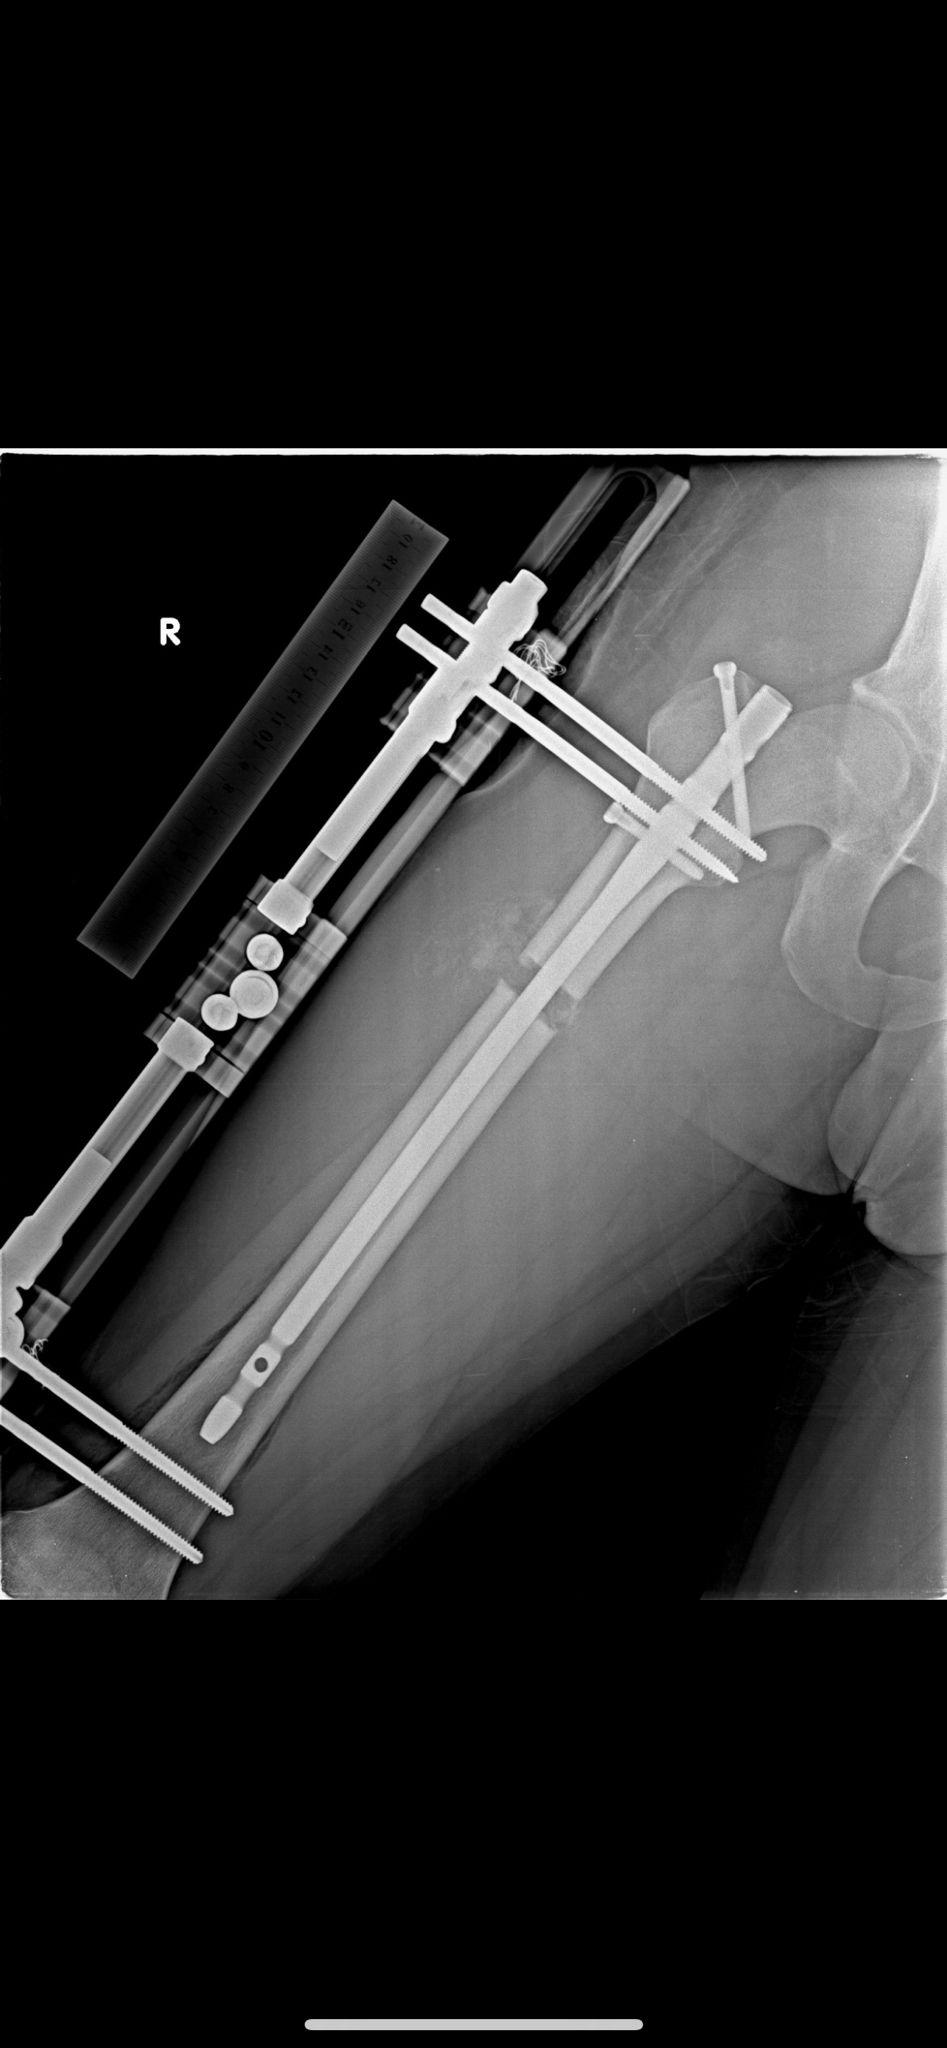

Yöntem ve Röntgen Görüntülerimiz

BAŞARILI SONUÇLARIMIZ

Boy uzatma ameliyatlarımızda kullandığımız modern yöntemlerin röntgen görüntüleri ve başarılı sonuçlarımızı inceleyebilirsiniz.

Fitbone Yöntemi

Fitbone® Yöntemi ile Boy Uzatma Tamamen İçten (Internal) Motorize Uzuv Uzatma Teknolojisi